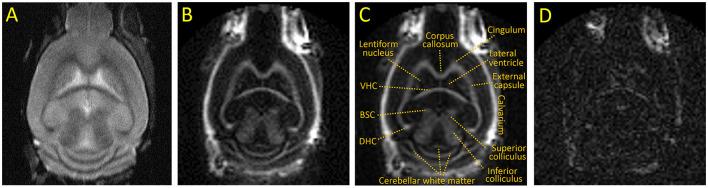

Non-aqueous myelin protons have ultrashort Ts and are "invisible" with conventional MRI sequences but can be detected with UTE sequences. The IR-UTE sequence uses an adiabatic inversion-recovery preparation to suppress the long T water signal so that the remaining signal is from the ultrashort T myelin component. In this study, eight 8-week-old C57BL/6 mice were fed cuprizone ( = 4) or control chow ( = 4) for 5 weeks and then imaged by 3D IR-UTE MRI. The differences in IR-UTE signal were compared in the major white matter tracts in the brain and correlated with the Luxol Fast Blue histochemical marker of myelin.

IR-UTE signal decreased in cuprizone-treated mice in white matter known to be sensitive to demyelination in this model, such as the corpus callosum, but not in white matter known to be resistant to demyelination, such as the internal capsule. These findings correlated with histochemical staining of myelin content.

3D IR-UTE MRI was sensitive to cuprizone-induced demyelination in the mouse brain, and is a promising noninvasive method for measuring brain myelin content.